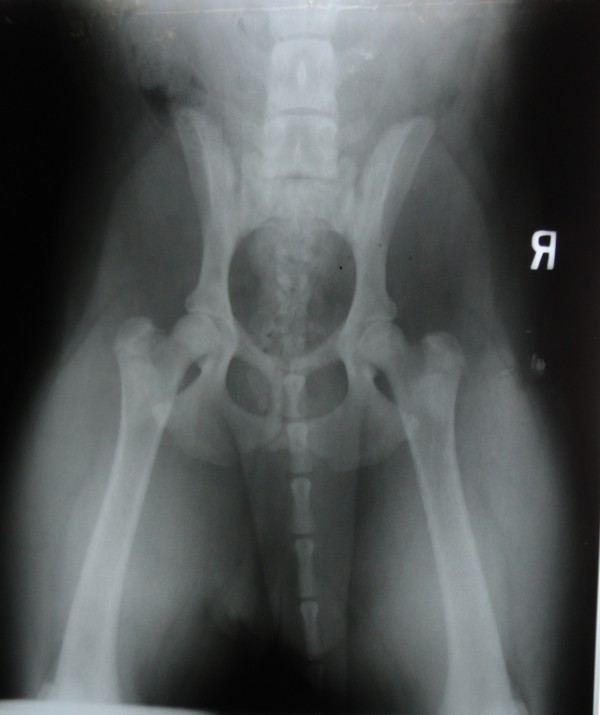

Más allá de las radiografías hechas con fines diagnósticos en los casos de animales enfermos en nuestra clínica tratamos de aplicar también el sistema del examen radiológico preventivo para diagnosticar enfermedades hereditarias, como por ejemplo la ¨displasia¨de cadera.